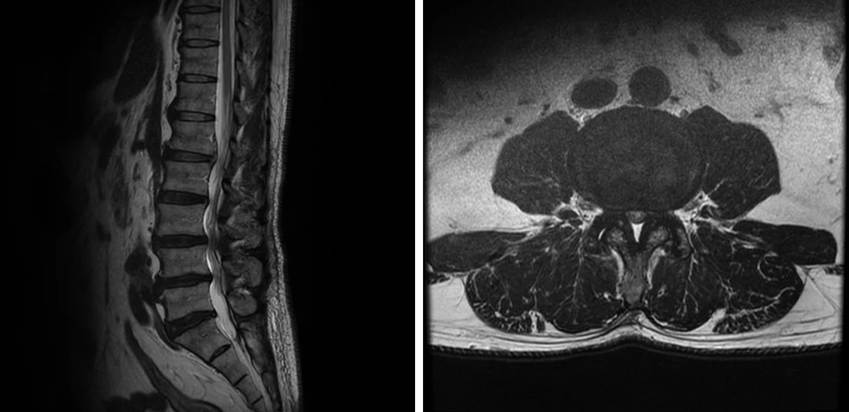

脊柱管狭窄症とは、神経の通り道である脊柱管が狭窄する(=狭くなる)ことにより、神経が圧迫される状態です。腰椎が不安定なことが原因の場合、身体の動きで痛くなることが多いです。

脊柱管狭窄症は、椎間板がひび割れることで中心成分が飛び出し、その飛び出した部分が脊柱管を狭くすることで起こります。椎間板のひび割れは修復できていなければ、再度ヘルニアが発生したり、再度脊柱管が狭くなったりしてしまう可能性があります。

当院のセルゲル法では、椎間板のひび割れ部分を埋める薬剤を注射し、それがゲル状になってひび割れを補綴するため、根本的な治療を行うことができます。椎間板のボリュームが減少することがなく、治療後に薬剤がゲル状のインプラントとして椎間板に残りますので、椎間板が温存されることが特徴です。